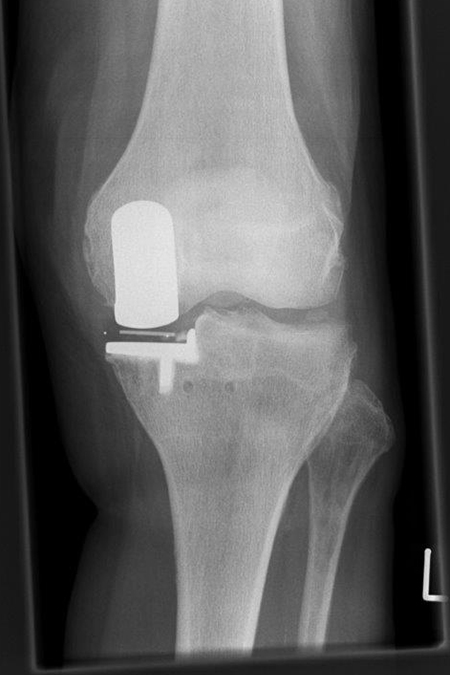

81-jährige Patientin mit innenseitiger Arthrose des linken Kniegelenks. Wir implantierten eine Schlittenprothese. Die Patientin demonstrierte im März 2021 ein gutes Gangbild mit nahezu freier Kniegelenksbeweglichkeit.

OXFORDSCHLITTEN

innenseitige Kniegelenksarthrose

OP Planung

Nach der OP (Oxfordschlitten)